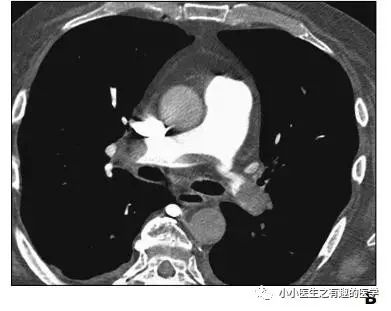

作者单位:Department of Radiology, University of Washington MedicalCenter, University of Washington School of Medicine。华盛顿医科大学。

翠花上菜,学者上图。

发现嫌疑犯,立即逮捕。

增强CT对比,一目了然。

上面的病人,增强CT放大了。